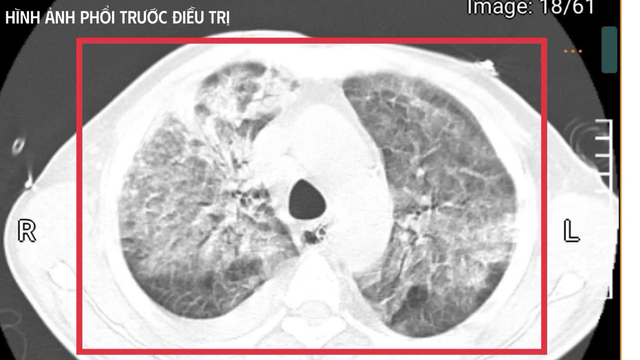

Hình chụp phổi của bệnh nhân trước khi điều trị

Khi tiếp nhận bệnh nhân tại Khoa Cấp cứu, Bệnh viện Bệnh Nhiệt đới Trung ương, ThS.BSNT Nguyễn Kim Anh mô tả đó là "khoảnh khắc rất căng thẳng". Anh T. hôn mê sâu, mất phản xạ đường thở và phụ thuộc hoàn toàn vào máy thở. Nhiệt độ cơ thể duy trì 41–42°C, run cơ toàn thân - dấu hiệu gợi ý tăng thân nhiệt ác tính trên nền nhiễm khuẩn huyết tối cấp. Xét nghiệm cho thấy hàng loạt chỉ số suy sụp như men gan tăng cao, rối loạn đông máu, biểu hiện suy gan, suy thận cấp tiến triển... Nhiều dấu hiệu phản ánh mức độ nhiễm trùng - nhiễm độc khốc liệt. Cùng với đó là bệnh nền đái tháo đường chưa kiểm soát và viêm gan C mạn khiến cơ thể càng suy kiệt.